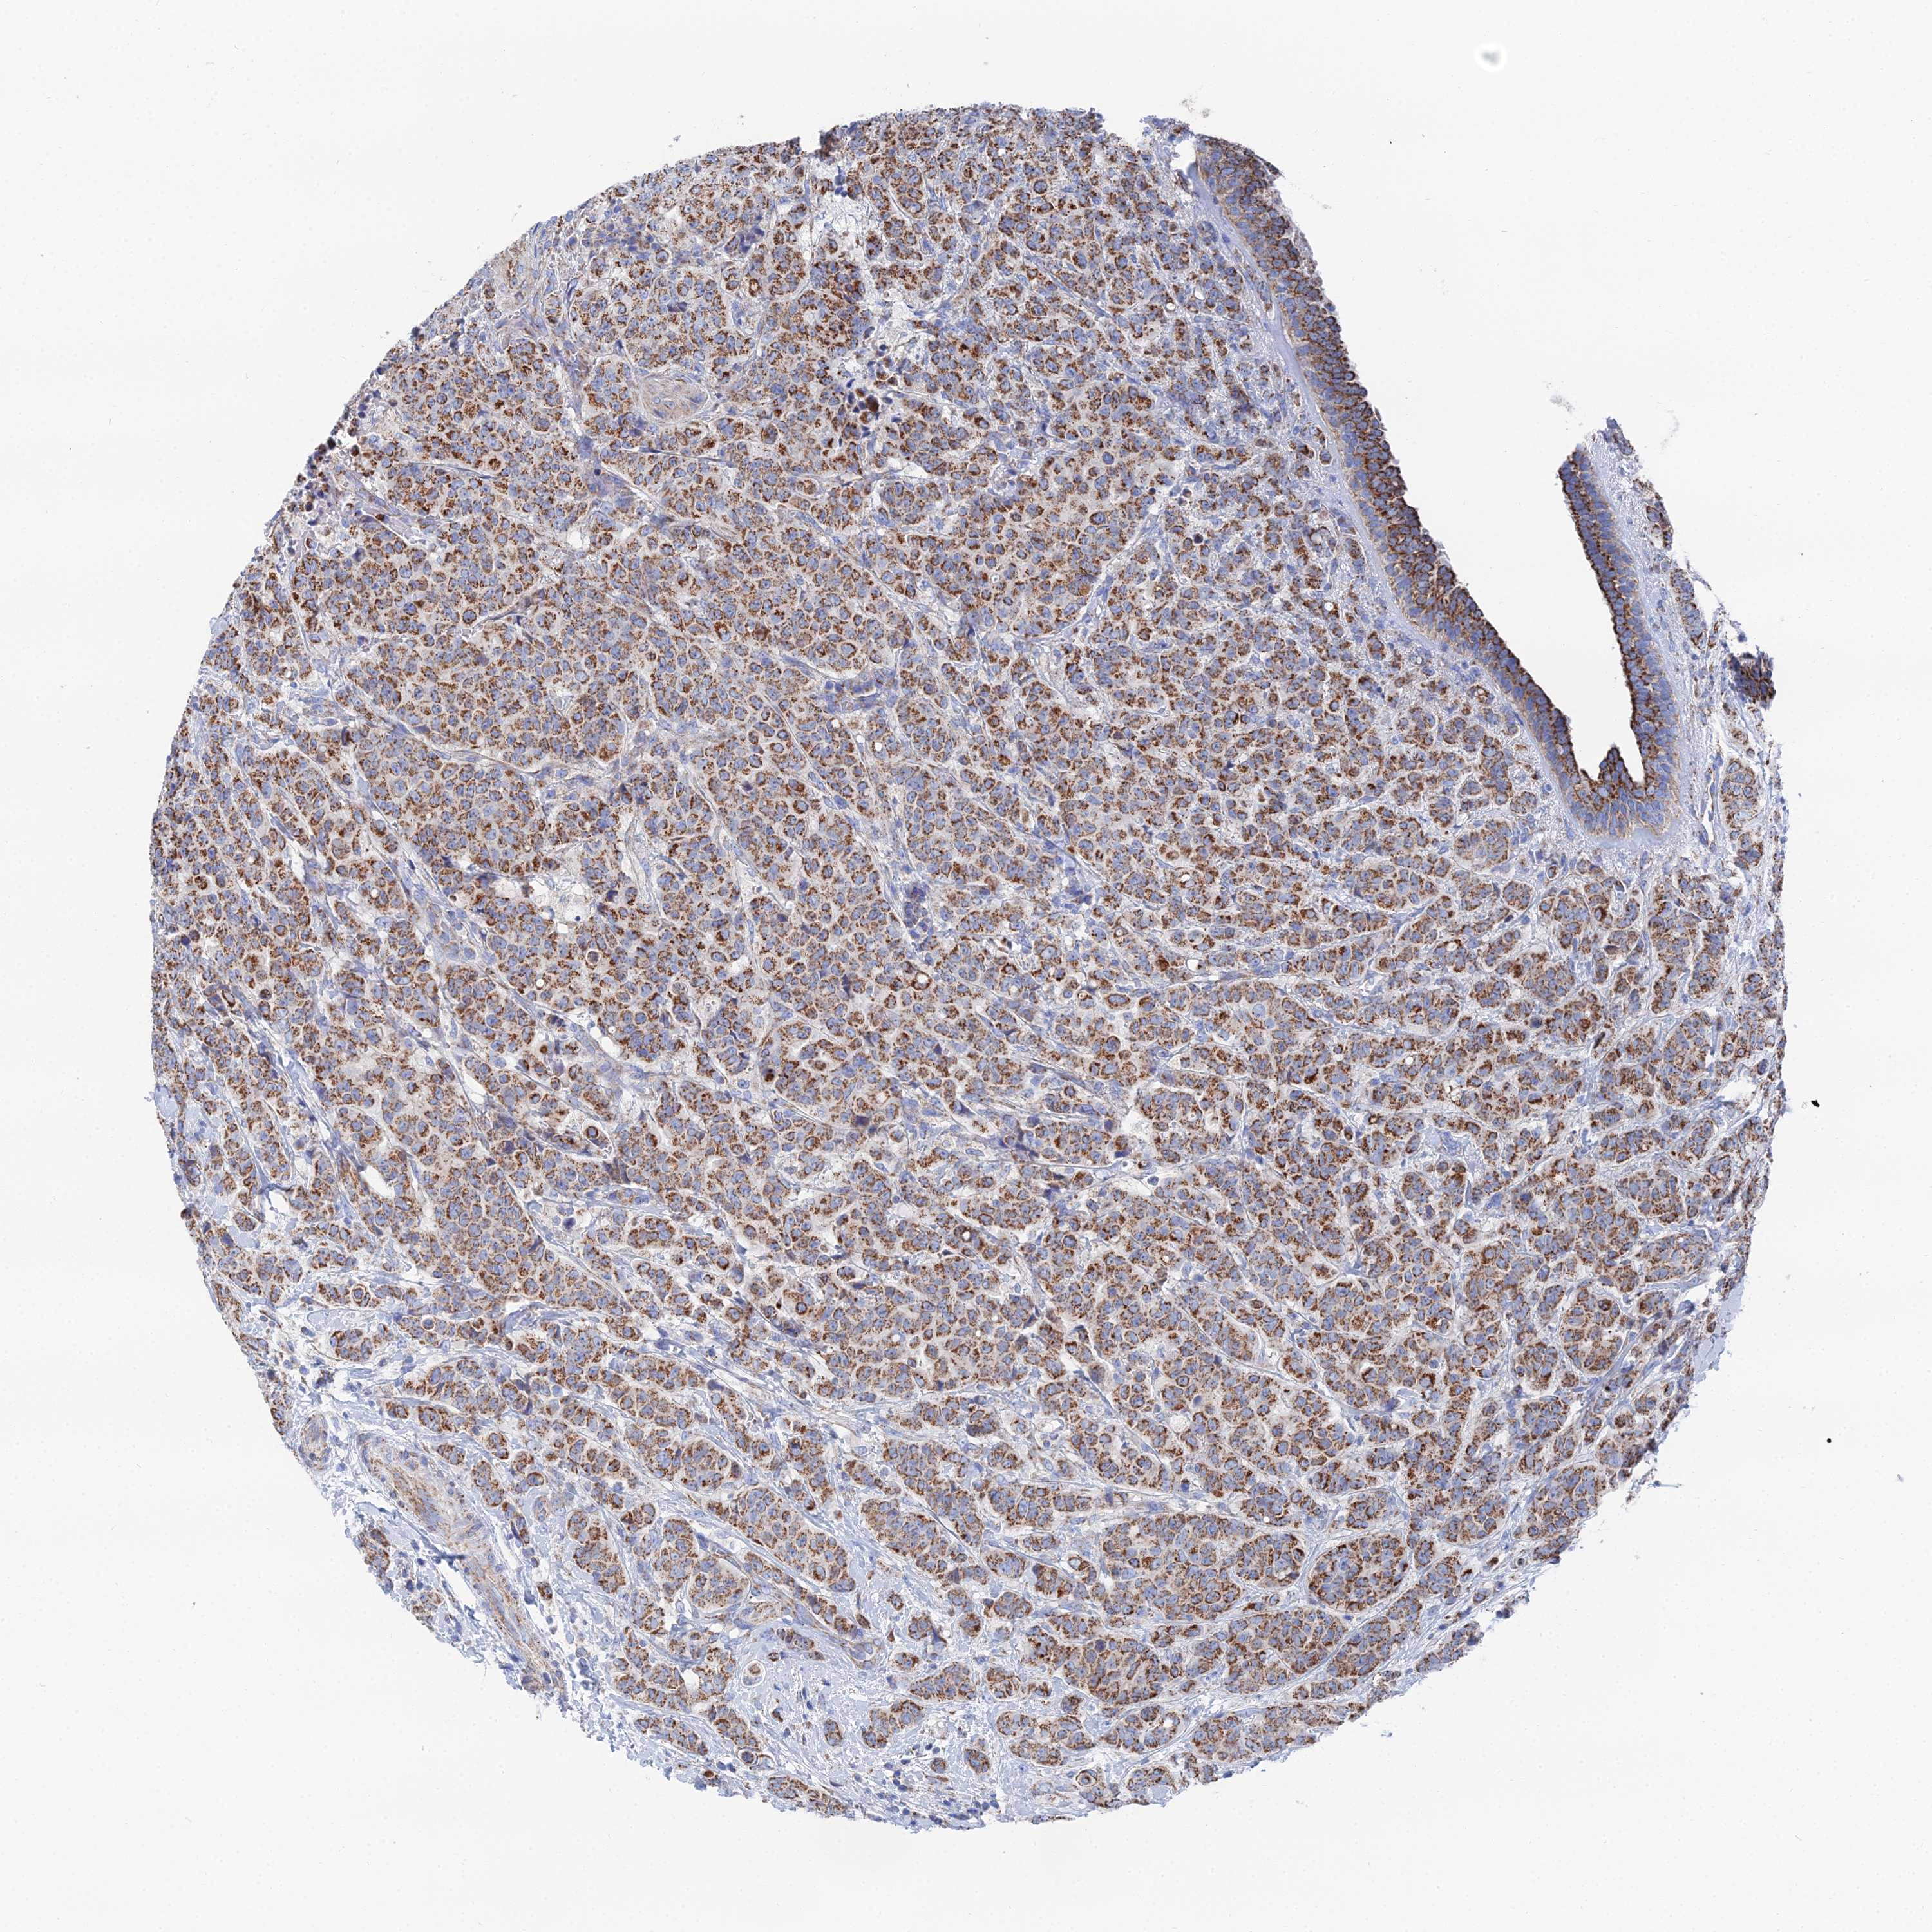

CANCER BREAST CANCER Show tissue menu

BRCA TCGA BRCA VALIDATION PROTEIN EXPRESSION

Breast cancer

Human cancer